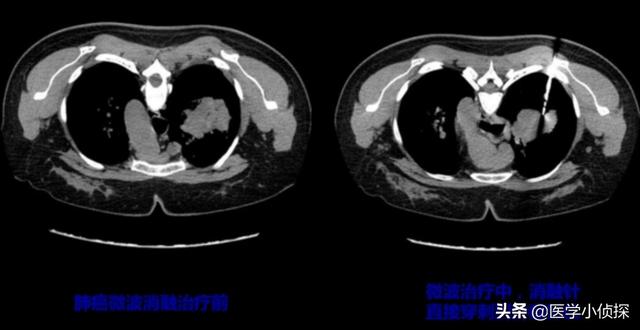

un type deMétastases osseuses seulesIl s'agit souvent d'une simple destruction osseuse locale, d'une douleur, cette fois-ci nous pouvons utiliser un traitement local peu invasif, l'effet est encore très bon, comme l'apparition de côtes, de vertèbres métastasées, nous pouvons utiliser une aiguille d'ablation à micro-ondes.

L'autre cas est plus problématique dans la mesure où il transfère un large éventail d'activités de l'Union européenne.À l'heure actuelle, nous disons que le traitement par ablation unique est plus difficile à faire jouer à l'effet, comme si, en cas de douleur à plusieurs endroits, vous vous contentez d'utiliser localement des analgésiques, l'effet est alors limité. Nous devrions alors utiliser un traitement intégré, tel que l'utilisation de médicaments pour inhiber la destruction osseuse, en même temps, il est très important de cibler également le cancer du poumon, l'utilisation de la chimiothérapie, des médicaments de ciblage, etc. pour le traitement de la cause profonde du problème, bien sûr, il y a aussi la possibilité d'utiliser le ciment osseux pour renforcer les os. Bien entendu, il est également possible de recourir à un traitement de renforcement par ciment osseux, qui peut réduire la douleur locale en renforçant les os.Mais en fin de compte, il s'agit toujours de traiter la cause première, c'est-à-dire de guérir le cancer du poumon!